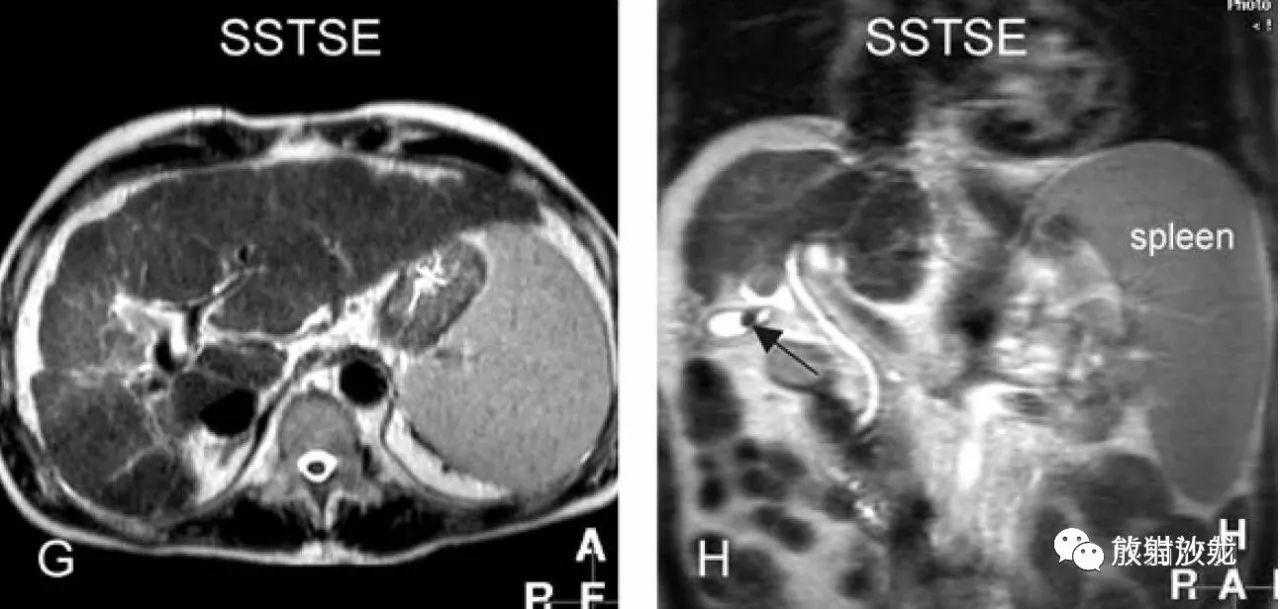

SSTSE:冠状T2WI,肝硬化,腹水,肝内多发低信号结节;

TSEfatsat:T2WI压脂,所有结节均呈低信号;

ART:动脉期,较大结节强化较明显,其余结节均不同程度有强化;

DEL:延迟期,大结节及其他结节均未见明显肿瘤包膜。

肝硬化,DN,MRI表现:

A~D:影像表现如上所述。